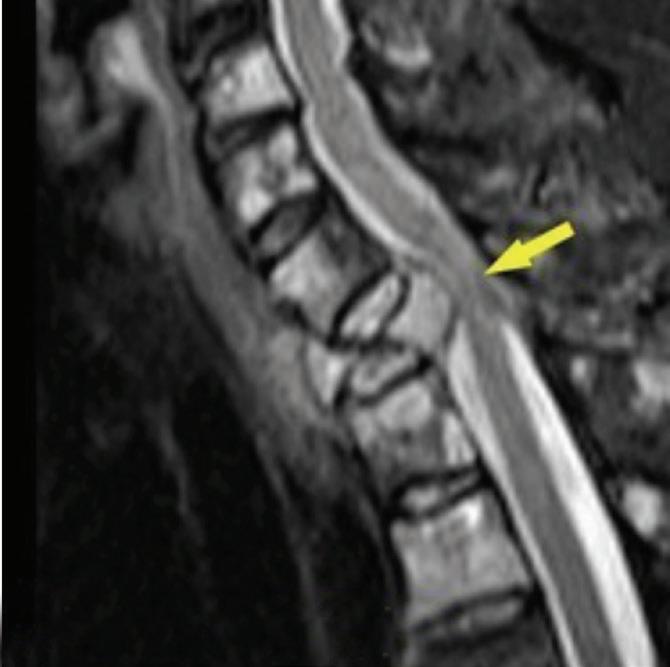

- Magnetic resonance imaging (MRI): This imaging device uses magnets and radio frequencies to make detailed images of organs and body structures.